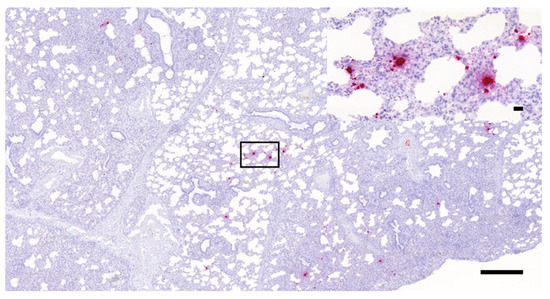

3.1. Histopathology and In Situ Hybridization